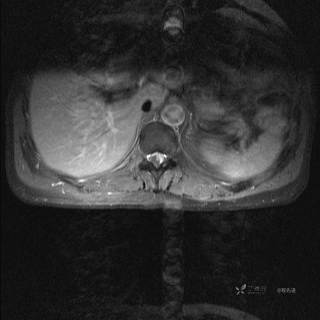

MR

T2

T2压脂

T1

T1增强

T1增强冠状位

T1增强横断位